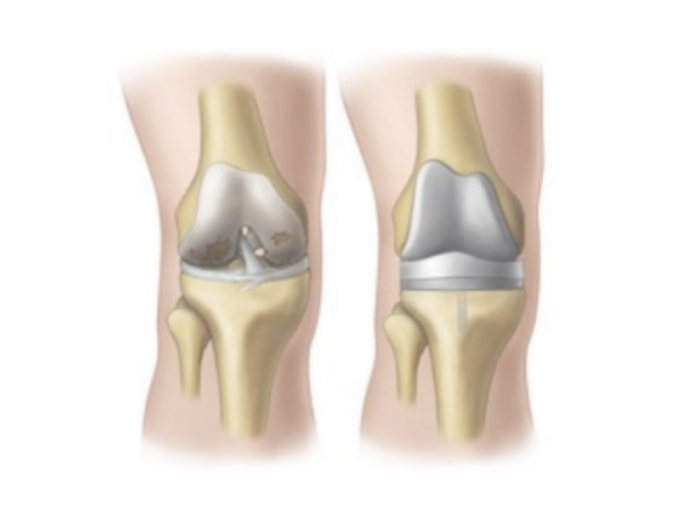

무릎 인공관절 수술은 퇴행성 관절염으로 인해 심각하게 손상된 무릎 관절을 인공 재료로 대체하는 고도의 의료 시술입니다.

이 수술은 주로 보존적 치료로 더 이상 효과를 보지 못하는 노년층 환자들에게 시행되며, 극심한 통증 완화와 일상 생활 기능의 회복을 주요 목적으로 합니다.

수술 과정에서는 손상된 연골과 뼈를 제거하고, 특수 제작된 금속이나 플라스틱 재질의 인공 관절로 대체하여 무릎의 정상적인 기능을 복원합니다.